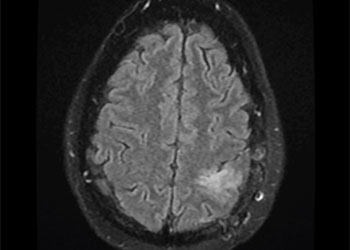

Brain:

Grade II Oligodendroglioma

Author: Ramin Rak M.D., F.A.A.N.S., F.C.N.S., Read More!